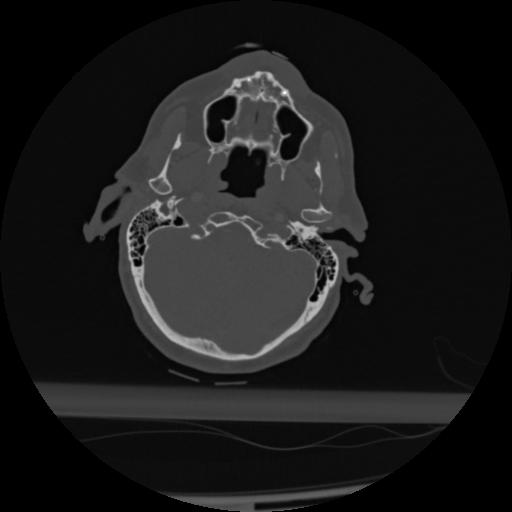

22 ANGIO,CE,Vol,0.5,ANGIO,,